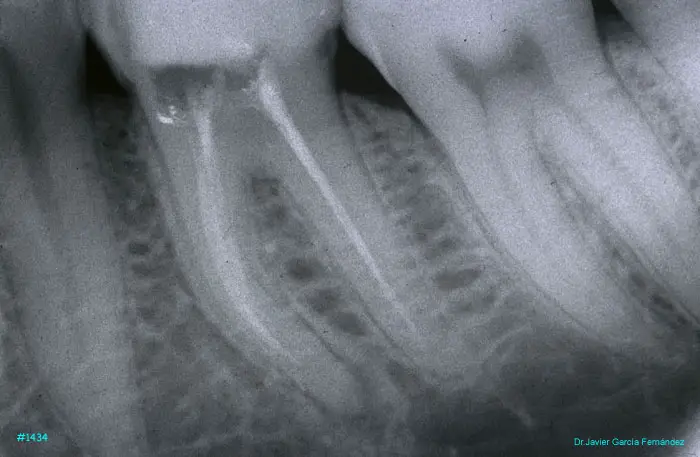

Atlas of Surgical Techniques in Periodontics. Chapter III. Atlas de Técnicas Quirúrgicas en Periodoncia